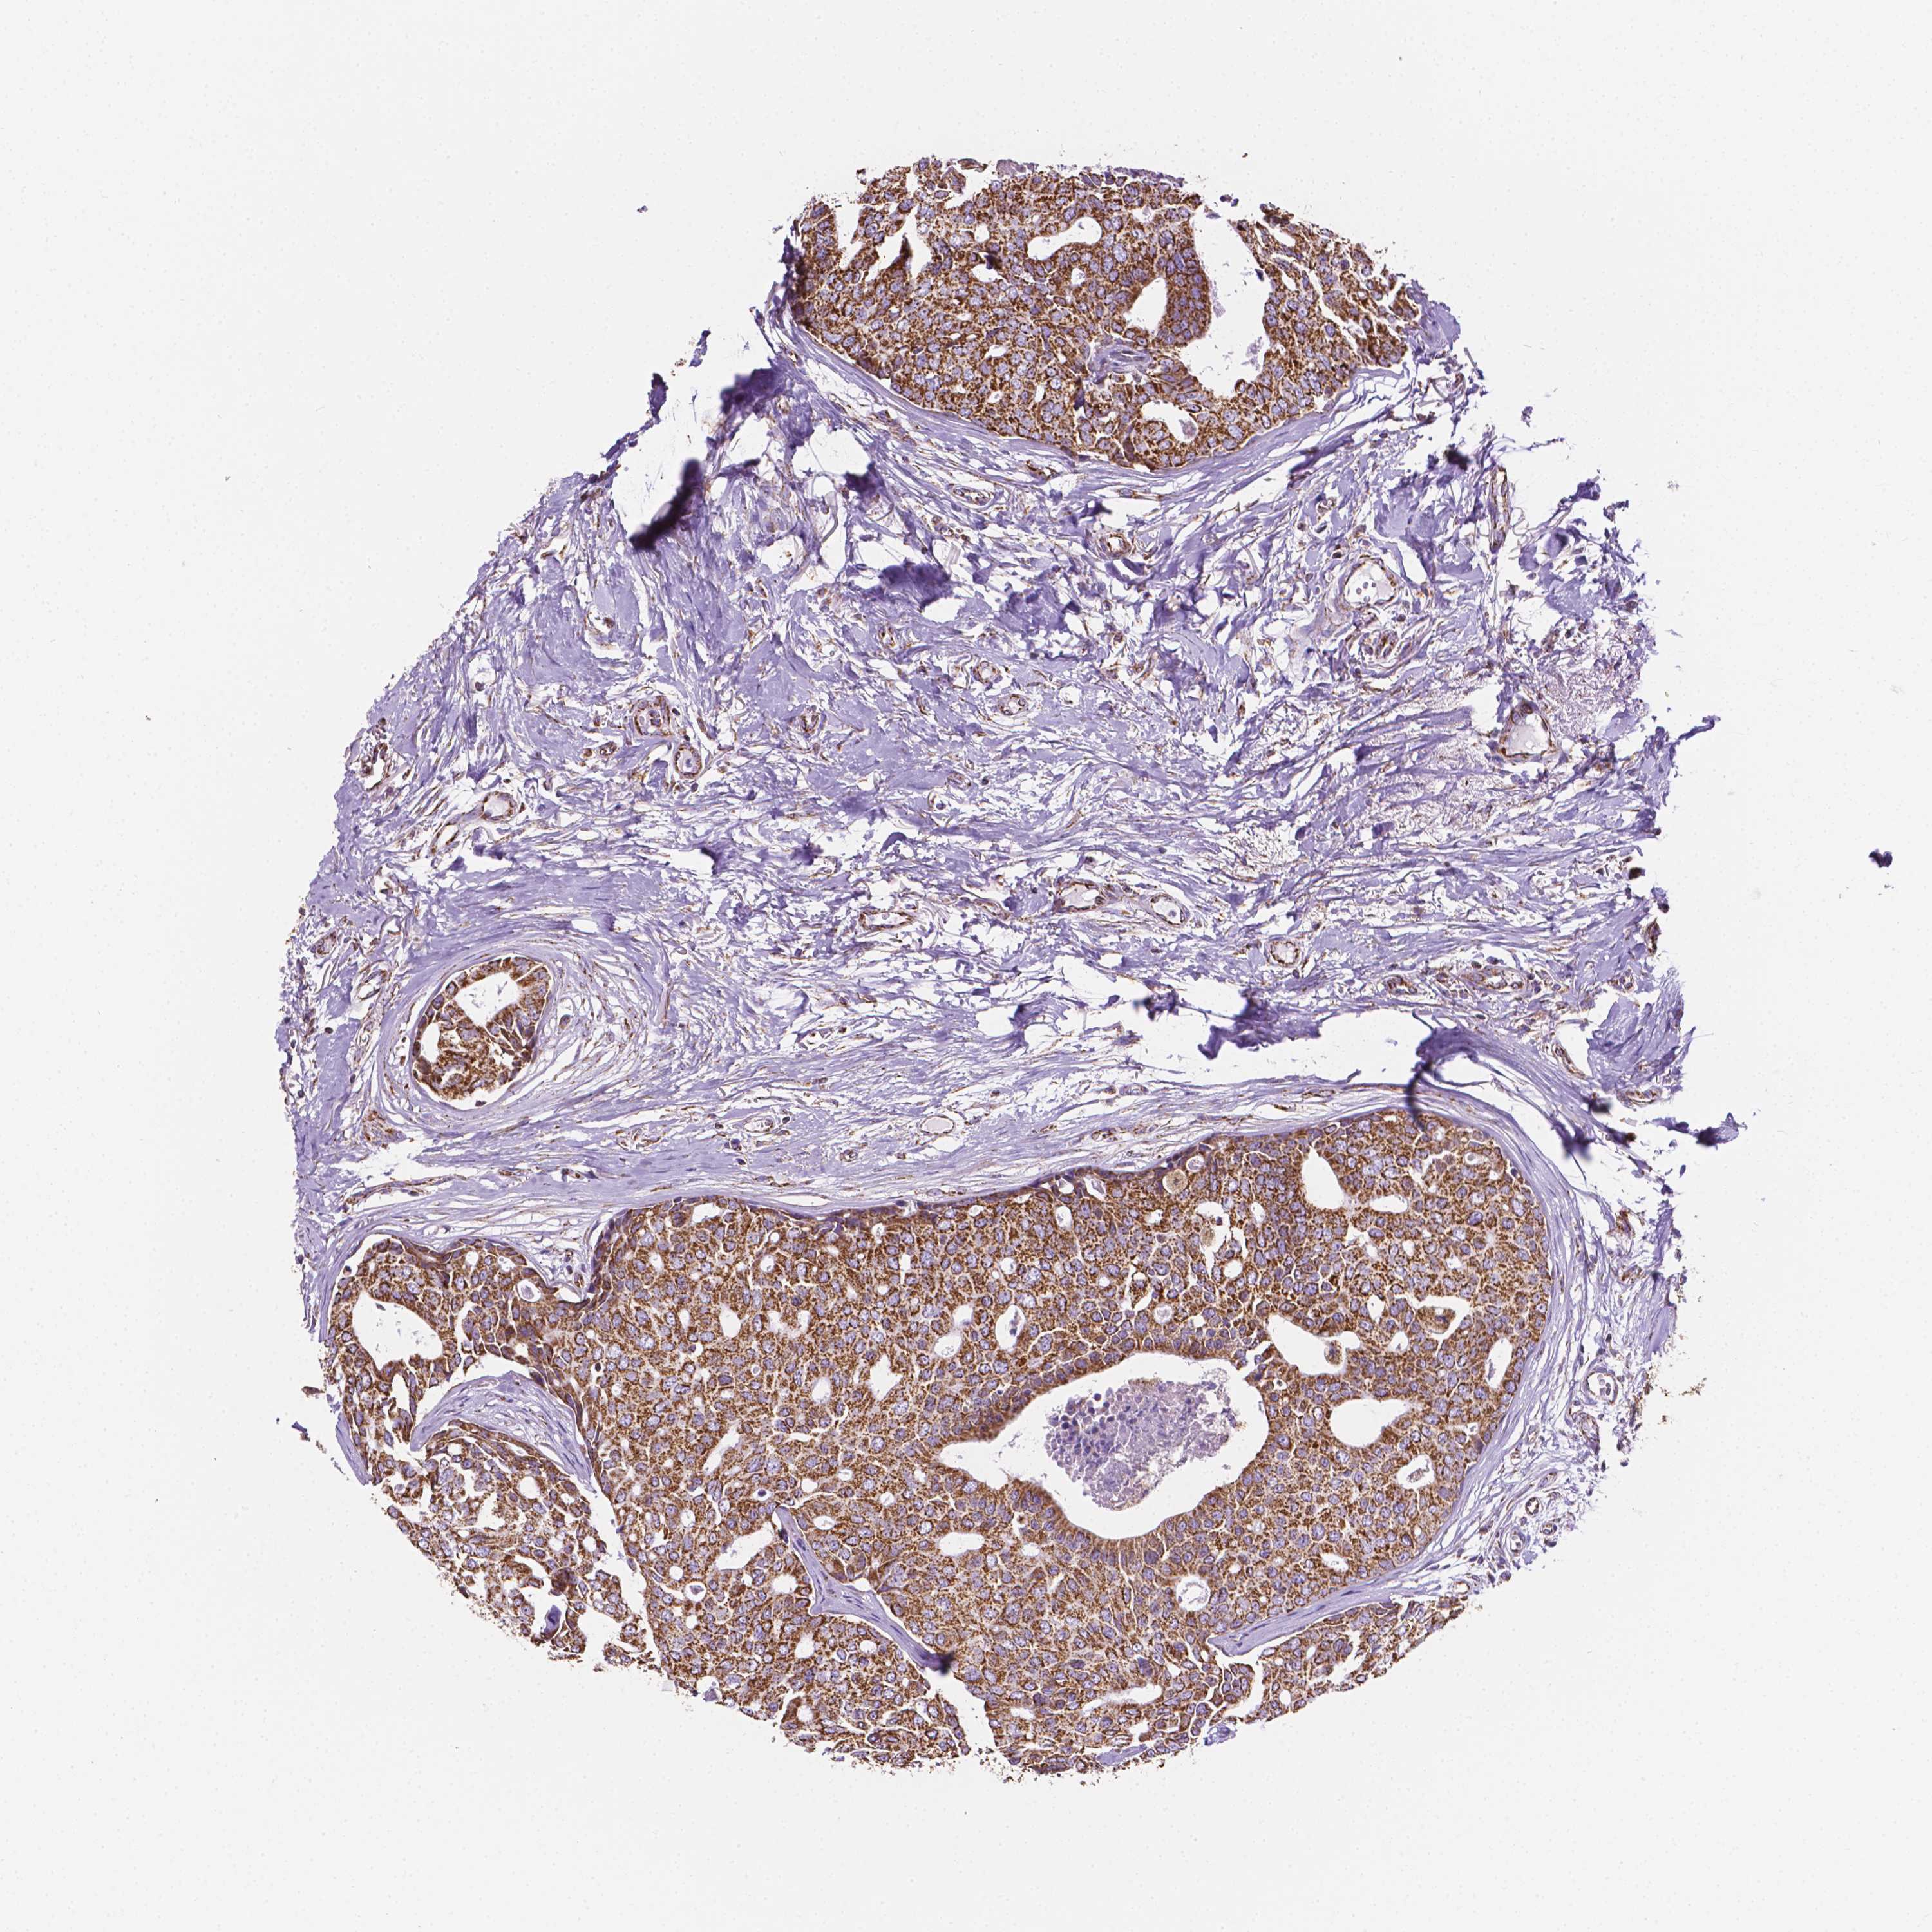

BRCA TCGA BRCA VALIDATION PROTEIN EXPRESSION

ANTIBODIES

AND

VALIDATION